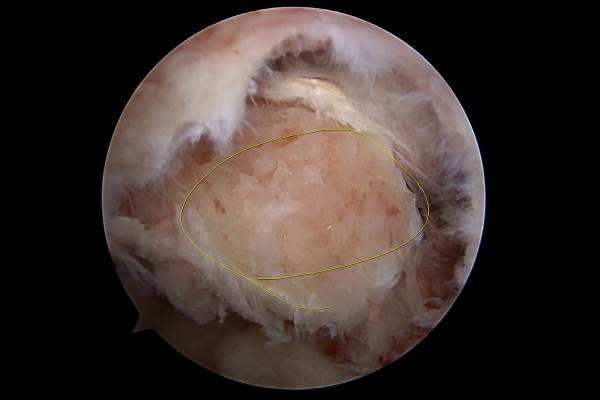

정확한 무릎 상태를 파악하기 위해서 촬영한 MRI 결과, 후방십자인대가 파열된 것이 확인되어 무릎 후방십자인대 파열(Posterior cruciate ligament rupture knee)을 진단하였습니다.

무릎의 뒤쪽에서 확인할 때의 내시경 사진입니다. 후방십자인대가 파열되어 보이지 않고 잔해만 남아있는 것이 확인됩니다.